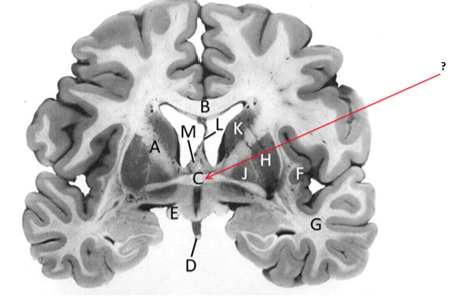

Name this and state its function.

Corpus Callosum.

Putamen.

Name this, state its function, pathways and cellular components.[5 marks]

Caudate nucleus.

Medium spiny neurons utilising GABA and some Cholinergic.

From cortex–>CN–>hippocampus, Gp and thalamus.

Septum pellucidum.

Fornix.

Anterior commissure.

Interconnects:

Infundibular stalk.

Insula.

Name this, state its function, components[2] and the difference in pathways.

Internal capsule.

Anterior limb:

Posterior limb:

Corticospinal tracts and corticopontine tracts: